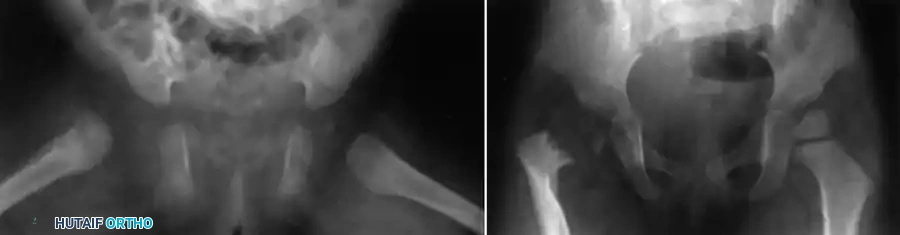

Fig. 16-3 Epiphyseal separation caused by infection in a young child. Note the catastrophic joint involvement secondary to transphyseal spread.